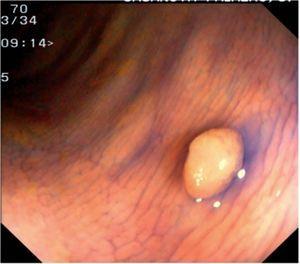

Fig. 3. Examples of flat lesions with conventional examination and after the application of indigo carmine 0.2-0.5%. a, b) Small flat adenoma, 3 mm in size. c, d) Large flat adenoma, 15 mm in size. e, f) Completely flat lesion (IIb in the Japanese classification). g, h) Depressed lesion, 3 mm in size) (IIc in the Japanese classification). I, J) Depressed lesion, 7 mm in size, histopathological study revealed submucosally invasive cancer (traditionally IIc in the Japanese classification, although recently such depressed lesions with a distinct central protrusion indicating submucosal invasion are termed IIc + Is). k, l) Flat elevated lesion with central depression, 10 mm in size, corresponding to a submucosally invasive cancer (IIa + IIc in the Japanese classification).